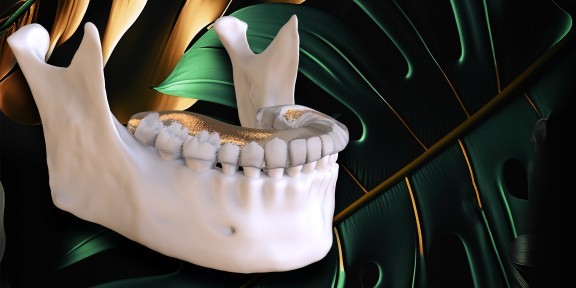

¡Protocolos para el diagnóstico y tratamiento de las disfunciones temporomandibulares y el bruxismo en un concepto basado en la evidencia y representado por el destacado especialista Daniele Manfredini y su equipo (Anna Colonna y Fabio Carboncini)!

– protocolos para el diagnóstico y tratamiento de los trastornos temporomandibulares en un concepto basado en la evidencia

– protocolos del diagnóstico y tratamiento del bruxismo en un concepto basado en la evidencia

– protocolo prostodóncico para el tratamiento del bruxismo.